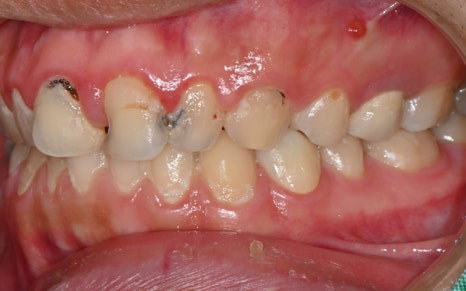

앞니 신경치료가

깔끔하게 마무리 된 모습입니다!

💛 앞니 심미 복원 💛

어느정도 치료를 진행한 후의 모습인데요.

무엇보다도 눈에 띄는 변화는

앞니의 심미 복원입니다.

하지만 치료 후 사진은

완전히 다른 사람이 된 듯한 변화가 느껴집니다.

마치 원래부터 예쁘고 반듯했던 치아처럼,

색상도 자연스럽고

모양도 얼굴형에 딱 맞게 복원되었습니다.